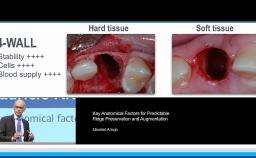

This lecture summarizes the morphological changes that follow tooth extraction and gives hints on how to minimize atrophy of the bony walls using atraumatic techniques and selected filling materials. Dr. Chen provides research evidence for various ridge preservation techniques and shares the characteristics of an ideal filling material. He also presents the clinical indications for each technique, including post-extraction ridge maintenance, immediate (Type 1) implant placement, and ridge reconstruction.

- describe the morphological changes of the alveolar walls after tooth extraction

- describe the effect of different filling materials on the bone resorption

- choose the optimal technique to minimize the resorption process